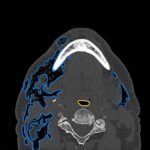

Subcutaneous emphysema (SE) is a rare but significant complication following dental procedures characterized by the presence of air in the subcutaneous tissue. This case report presents a 67-year-old male who developed right-sided facial swelling after tooth extraction, a procedure executed with high-power dental tools. Clinical findings included facial swelling and crepitus with no lip involvement, differentiating SE from an allergic reaction and hematoma. Diagnostic imaging through computed tomography (CT) and chest X-ray confirmed SE, showing diffuse subcutaneous air in facial and neck soft tissues. Initial management in the emergency department (ED) involved administration of antihistamines, corticosteroids, antibiotics, and otolaryngology (ENT) consultation with close monitoring for airway compromise. This case underscores the importance of including SE in differential diagnoses for post-dental procedure swelling, the effectiveness of CT imaging in SE identification, and the importance of early detection and treatment to prevent severe complications like respiratory and cardiac issues.